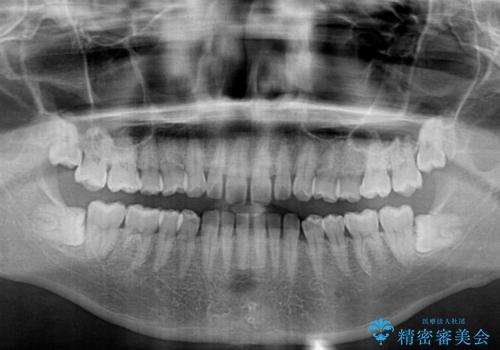

- 上下前歯の隙間を気にして来院された患者様です。

飲み込みや話をするときに舌を突出させる癖が強くあり、それが原因でスペースが空いていました。

舌癖を改善するためのトレーニングを行いながら、ワイヤー装置を用いて前歯の隙間を閉じていくこととしました。